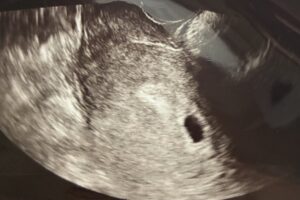

妊娠4〜5週、胎嚢だけ確認

最初の診察では胎嚢のみ確認。

4〜5週ですね。2週間後に来てください

小さなお部屋みたいな丸い袋。